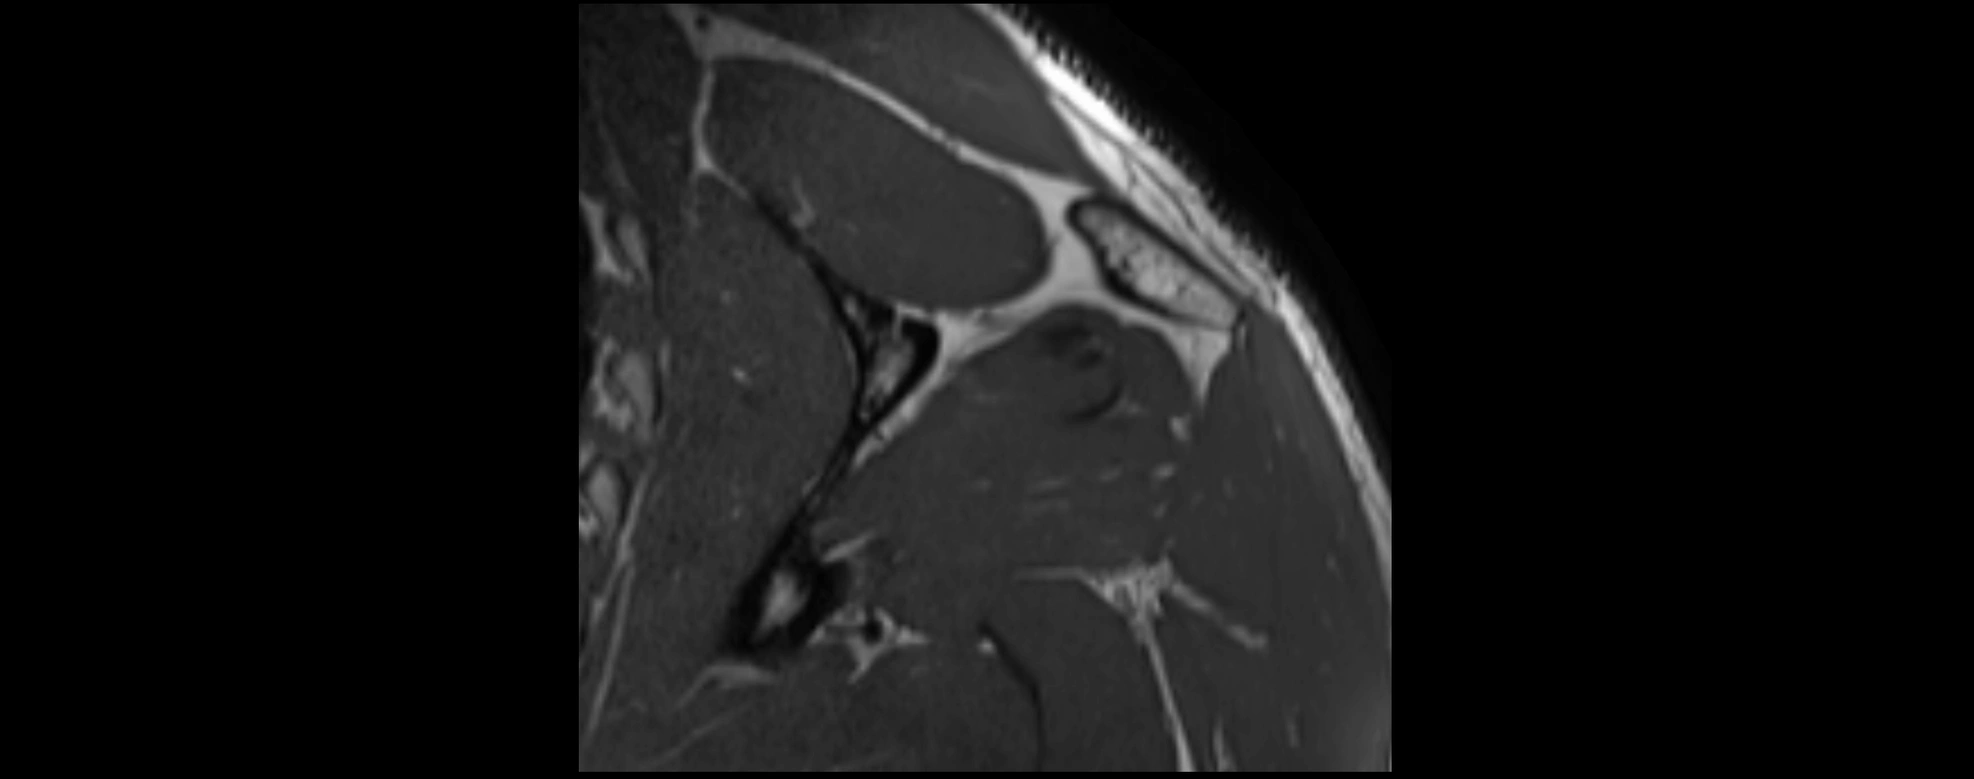

MRI images

image